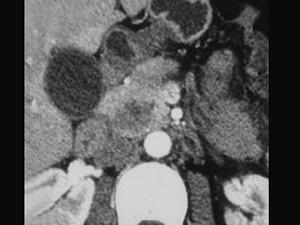

问题 女,56岁,腹部胀痛不适、食欲减退,影像表现如下图,最佳诊断是 ( )

选项 A、胰腺转移癌 B、胰腺假性囊肿 C、慢性胰腺炎 D、胰腺腺癌 E、急性胰腺炎

答案 D